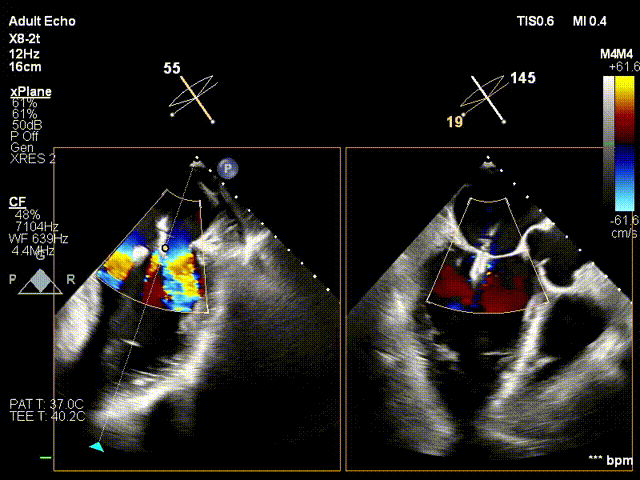

术前术后反流对比:三尖瓣反流4+下降至1+

术前反流

术后反流